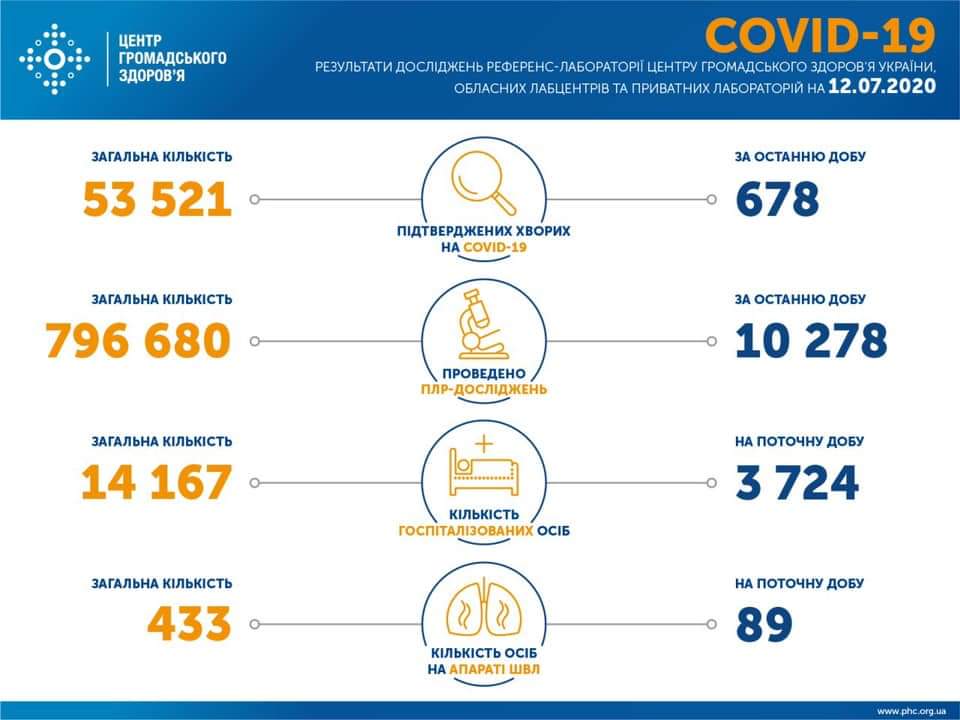

МОЗ: Уперше з початку пандемії було зроблено понад 100 тисяч ПЛР-досліджень за добу

Більше 3 тисяч випадків захворювання на коронавірус зафіксували в Україні за добу

11.09.2020 09:37